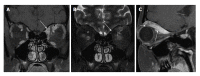

Orbital inflammatory disease (OID) represents a collection of inflammatory conditions affecting the orbit. OID is a diagnosis of exclusion, with the differential diagnosis including infection, systemic inflammatory conditions, and neoplasms, among other conditions. Inflammatory conditions in OID include dacryoadenitis, myositis, cellulitis, optic perineuritis, periscleritis, orbital apicitis, and a focal mass. Sclerosing orbital inflammation is a rare condition with a chronic, indolent course involving dense fibrosis and lymphocytic infiltrate. Previously thought to be along the spectrum of OID, it is now considered a distinct pathologic entity. Imaging plays an important role in elucidating any underlying etiology behind orbital inflammation and is critical for ruling out other conditions prior to a definitive diagnosis of OID. In this review, we will explore the common sites of involvement by OID and discuss differential diagnosis by site and key imaging findings for each condition.